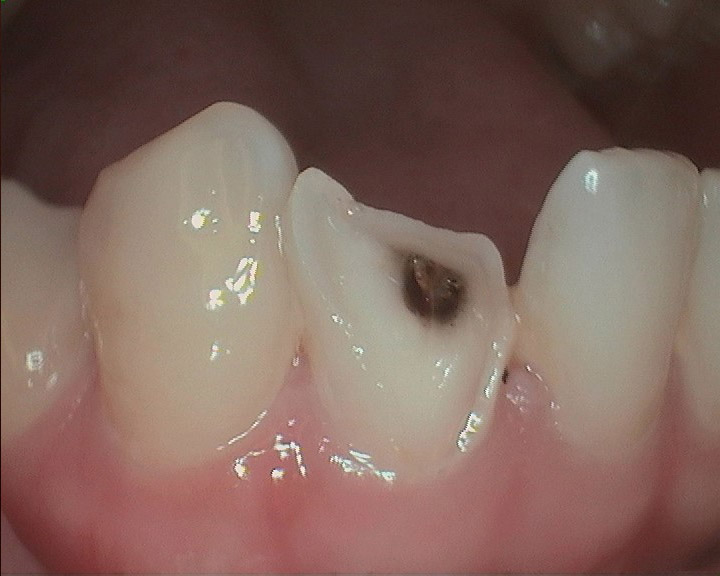

Crown Replacement.

Replaces poor crown margins. Help remove dental decay and restores teeth.

Before: Old bad shaped crown with margin caries

After: New crown with our CEREC technology. Give your tooth a natural look!